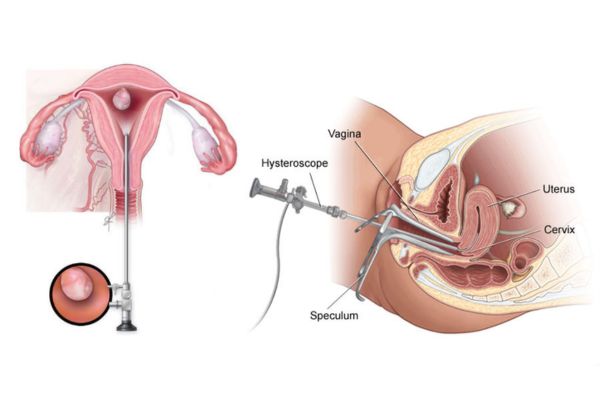

Ovulation induction, IUI, hormonal therapy & laparoscopic/ hysteroscopic procedures for fertility enhancement.

Diagnosis and surgical correction of congenital or acquired uterine abnormalities for improved reproductive health.

Diagnostic and operative procedures for uterine abnormalities, polyps, and fibroids.

Removal of the uterus through the vaginal route for conditions like fibroids, prolapse, or abnormal bleeding.